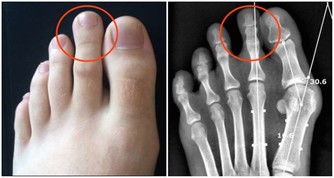

病理性小便分叉是由疾患引起的,除前列腺增生外,其他疾病如急性尿道炎或急性前列腺炎,由於尿道充血、腫脹,分泌物增多,也會導緻小便分叉。

損傷或炎症導致的尿道狹窄,如尿道內的損傷或損傷後的繼發感染、反復發作的尿道炎等,造成尿道內膜組織形成瘢痕,使局部尿道管腔變得狹窄,尿液排出不暢,同樣會出現小便分叉。

另外,包皮過長、包莖、陰莖炎症以及泌尿系感染、尿道結石也可能出現小便分叉,後者常伴有尿急尿痛等其他不適。